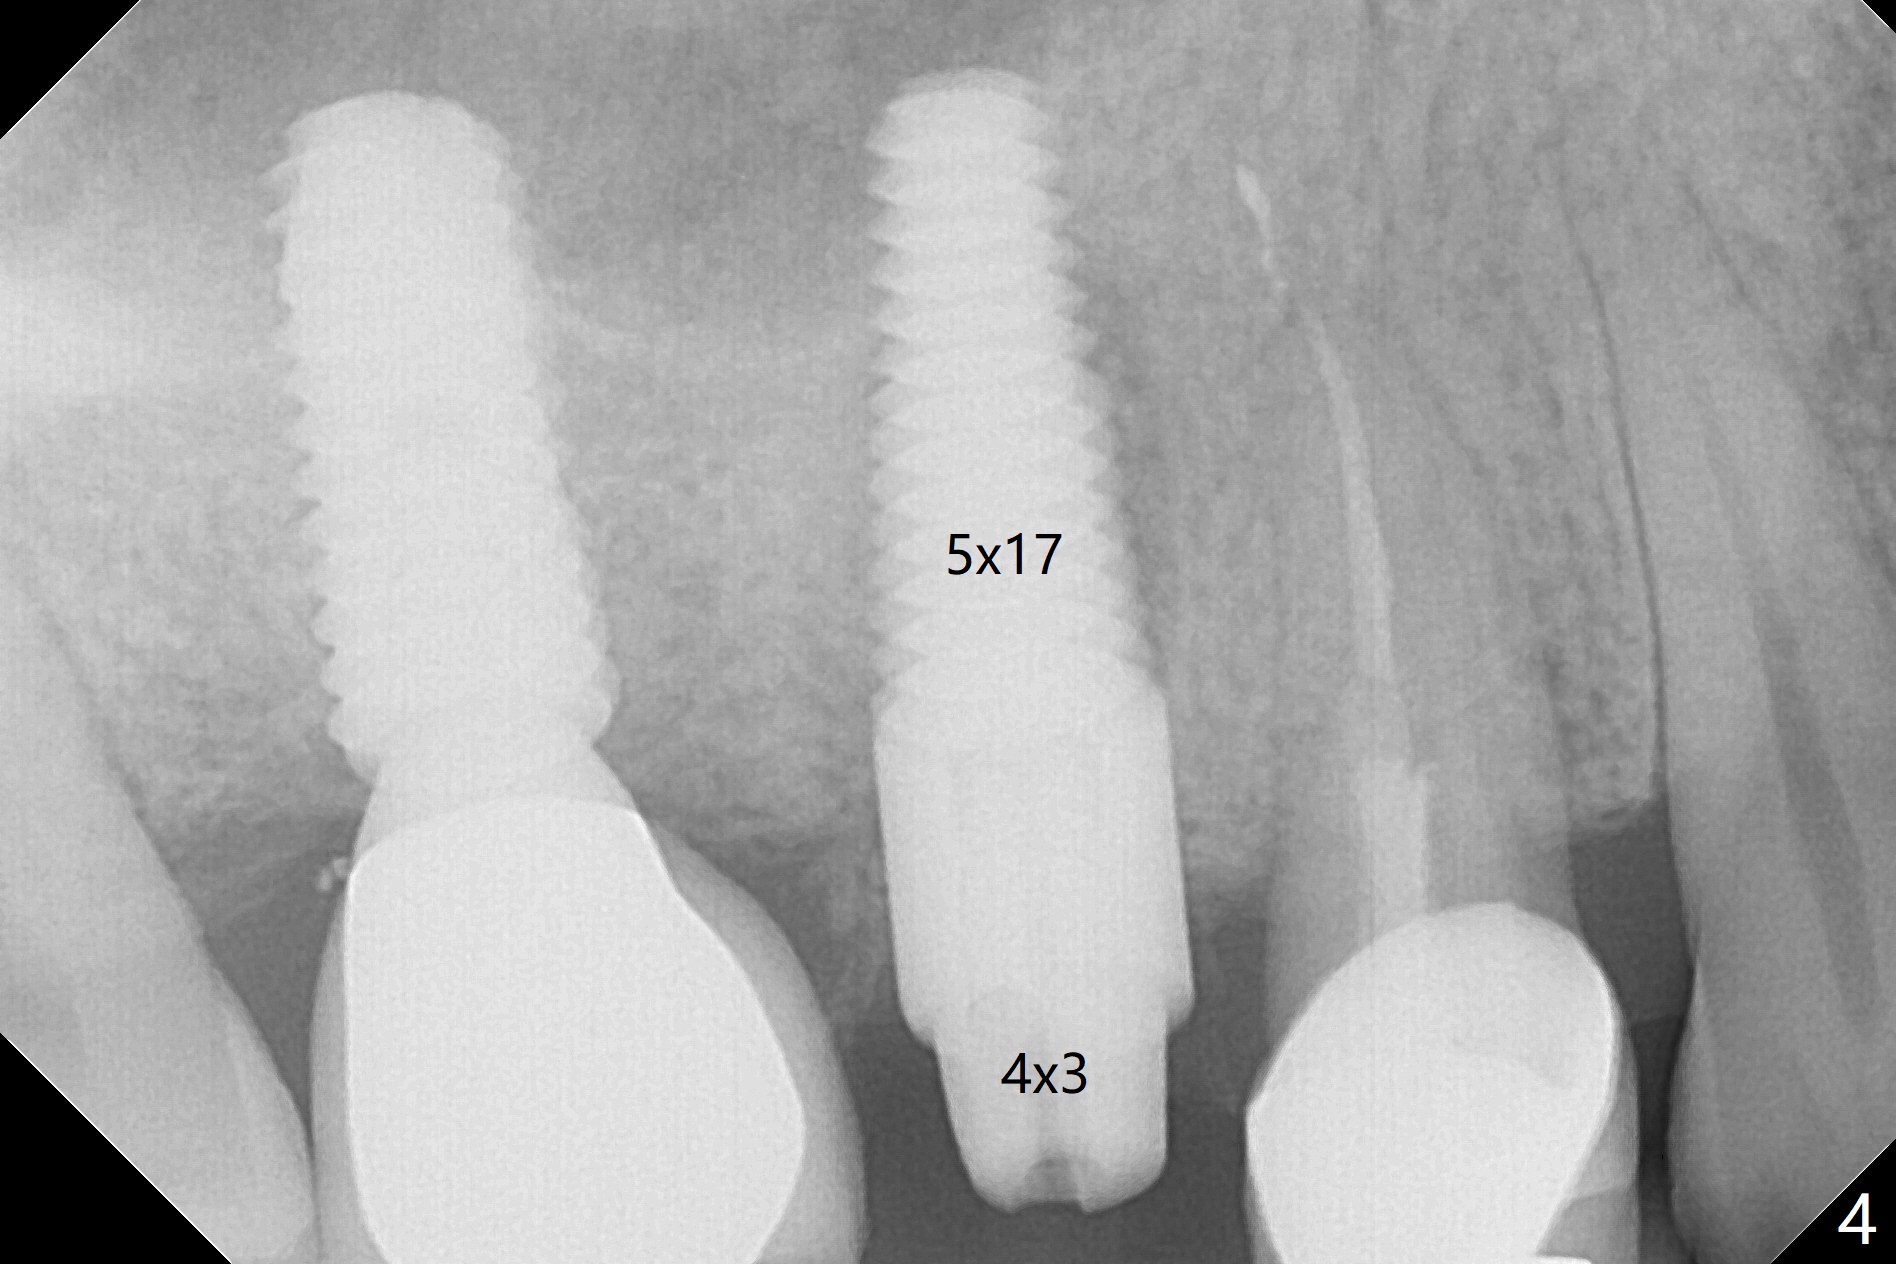

In spite of a fistula at #4, the buccal plate is present because of the exostosis (Fig.1 *). Since the socket is long and narrow, it is difficult to initiate osteotomy in the distal slope. Since the buccal plate is low, osteotomy is established as palatal as possible. The sinus floor is thin, but hard to elevate with Magic Sinus Lifter. Use of 3 mm Magic Expander leads to sinus floor break through and membrane perforation. After increase in the osteotomy with sequential expanders, a 5x20 mm tap is inserted with stability (Fig.2). Two pieces of PRF membrane are inserted for sinus membrane repair, followed by small amount of allograft (mixed with PRF, Fig.3 *) and a 4.5x17 mm dummy implant. A 5x17 mm tissue level implant is placed with >45 Ncm; with immediate placement of a 4x3 mm abutment (Fig.4), an immediate provisional is fabricated. There is no postop nasal hemorrhage. The immediate provisional has occlusal perforation 1.5 months postop. The tooth #13 has mobility due to its overuse and missing the teeth #14 and 18. Bitewing taken while redoing crown for #30 shows that the implant threads are subcrestal (Fig.5). There is no crestal bone resorption 6.5 months postop (Fig.6,7), while the periradicular radiolucency decreases (Fig.7).